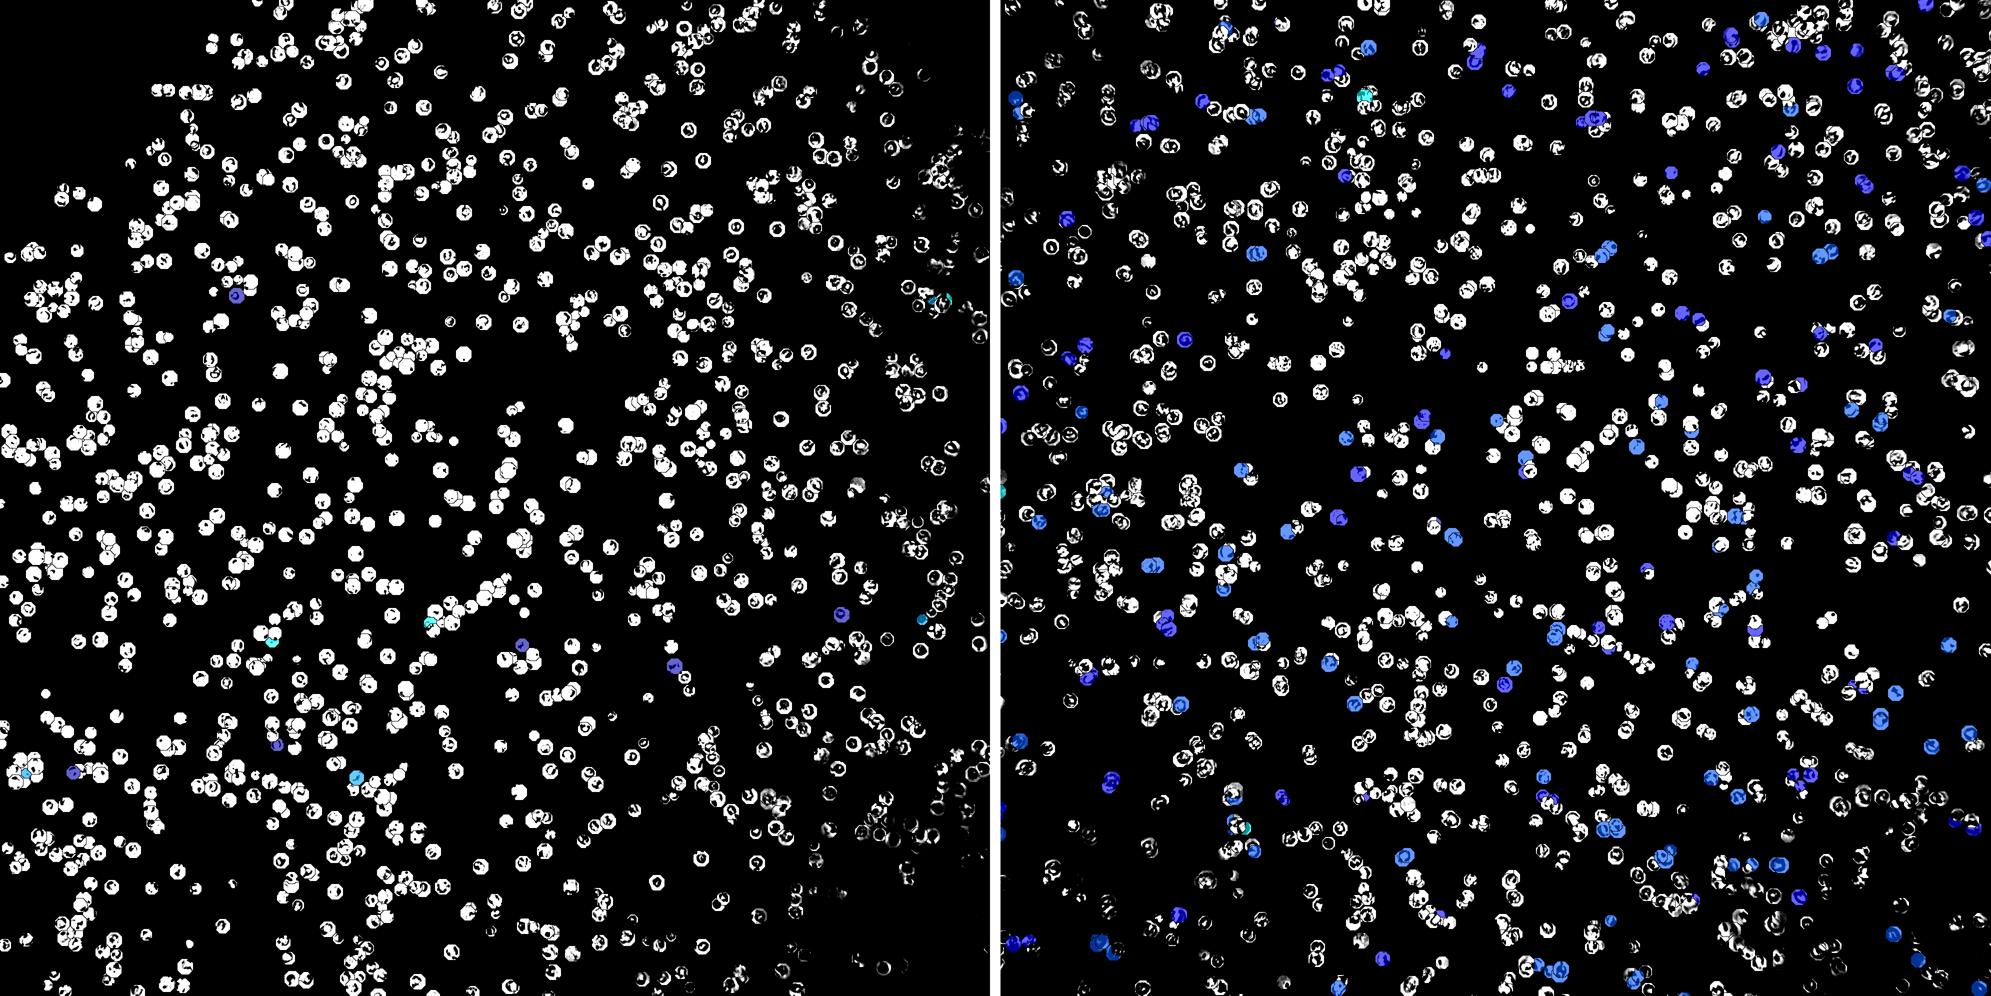

Cells labelled with CD8a TIA1

Peripheral blood lymphocytes

Inflammatory Disease

Cell populations before and after treatment